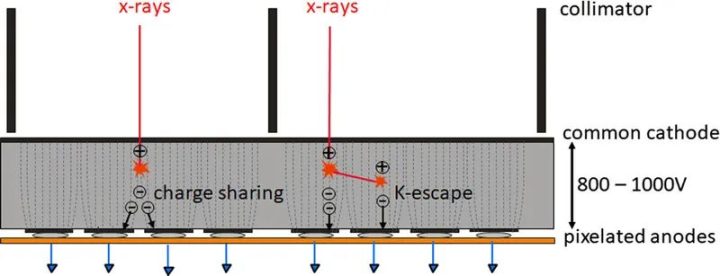

为了获得光谱分辨数据,需要同时读出在不同阈值能量下工作的多个计数器,见图2。然后,探测器为每个阈值提供单独的数据流,其中只包含能量超过相应阈值能量的X射线量子,另见图2。从包含能量超过最低阈值能量TL的所有X射线量子的数据流中重建的图像(TL图像,西门子公司专有,也称为T3D图像)可与传统CT在相同的X射线管电压(kVp)下获得的图像相媲美。然而,在现实的PCD中,由于不可避免的物理效应降低了信号的光谱分离度,如像素边界的电荷共享或荧光导致的X射线量子能量损失,能量登记存在误差。这些效应的示意图如图3所示,它们会导致量子在X射线能量过低时被错误地计数两次。与CdTe-PCD或CZT-PCD相比,硅PCD受电荷共享和荧光的影响较小,因此光谱分离效果较好,但大多数X射线量子主要在硅晶体中散射,而不是直接吸收;它们经常离开探测器像素而不产生信号,因此探测器的探测量子效率降低,所有探测任务都需要更高的辐射剂量。在非常高的X射线通量下,产生的电压脉冲在时间上重叠,不再单独计数。然而,在实际的CT通量率下,脉冲堆积并不起作用。

图3 电荷共享和K-escape的示意图,它们降低了现实PCD的能量分离。靠近像素边界吸收的X射线会产生电子,这些电子会在相邻像素中产生信号(电荷共享)。因此,一个X射线光子会以过低的能量被错误地计数多次。入射的X射线最初还会击穿探测器材料的内壳电子(K电子)。这会产生荧光辐射,荧光辐射会被探测器单元本身或邻近的探测器单元重新吸收和计数(K-逃逸)。入射到初级相互作用位点的X射线以过低的能量进行计数。